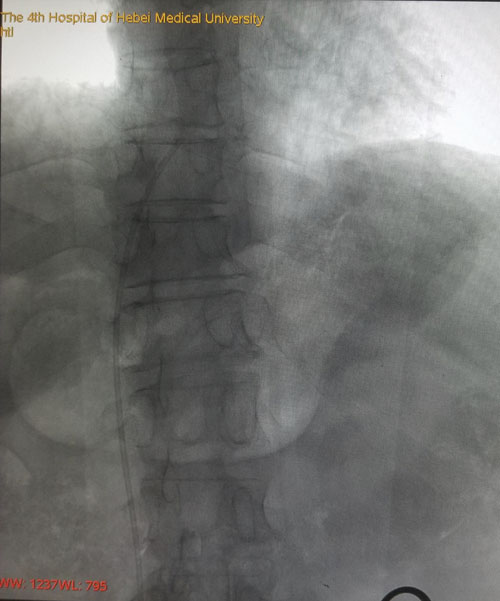

術(shù)后DSA評(píng)估導(dǎo)管尖端位置

本例患者由于是雙側(cè)乳腺癌術(shù)后伴雙側(cè)頸部及左胸壁廣泛轉(zhuǎn)移而來(lái)我院就診,難以建立常規(guī)輸液通路。乳腺中心回天立主管醫(yī)生通過(guò)查閱大量文獻(xiàn)資料并結(jié)合既往手術(shù)經(jīng)驗(yàn),與宋振川主任反復(fù)商討后制定了股靜脈港的置入方案。手術(shù)當(dāng)日,在超聲科紀(jì)曉惠主任、放射科楊光主任的協(xié)助下,成功將導(dǎo)管送達(dá)下腔靜脈與右心房結(jié)合部,港座埋置于右下腹壁皮下,完成了我省首例股靜脈穿刺靜脈港置入術(shù)。術(shù)后第一天患者恢復(fù)順利,下床活動(dòng)良好,靜脈通路順暢。